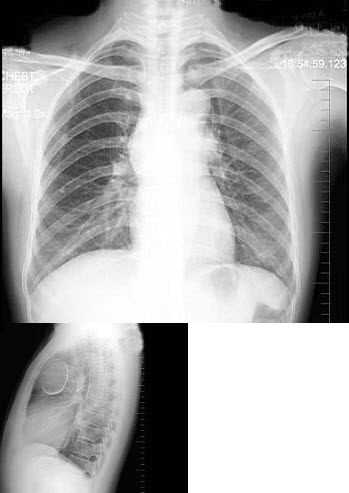

4、单项选择题

女,47岁,偶感胸闷,体检胸片如图,最可能的诊断是()

5、单项选择题

男,49岁,心前区阵发性绞痛10天。贫血面容,有胃病史。结合图像,最可能的诊断为()

15、单项选择题

男,38岁,感胸闷气逼2周余,近来加剧,不发热,X线检查如图,最可能的诊断是()

A.右侧肺不张

B.右侧胸膜肥厚

C.右侧大量胸腔积液

D.右侧中量胸腔积液

E.右侧气胸